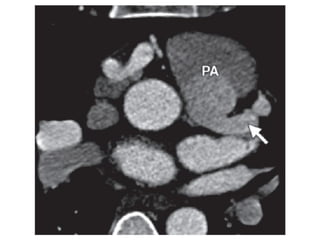

Compensatory dilatation •Fistula – Compensatory dilatation secondary to high-flow E state – originate from the RCA in 52% of cases; LAD 30%, and LCx 18%. – drainage is to right chambers, direct volume overload to the pulmonary vascular bed, the left atrium, and left ventricle; whereas if drainage to left cardiac chambers overload spares the pulmonary vasculature

• 44.

• Coronary ArteryAnomalies – eg. anomalous origin of the left coronary artery from the pulmonary artery (ALCAPA) syndrome (or Bland-White-Garland syndrome) – 1/300,000 live births – LM from PA  Ectatic RCA (due to elevate pressures)  R to L collaterals and steal phenomena in RCA terrirory E